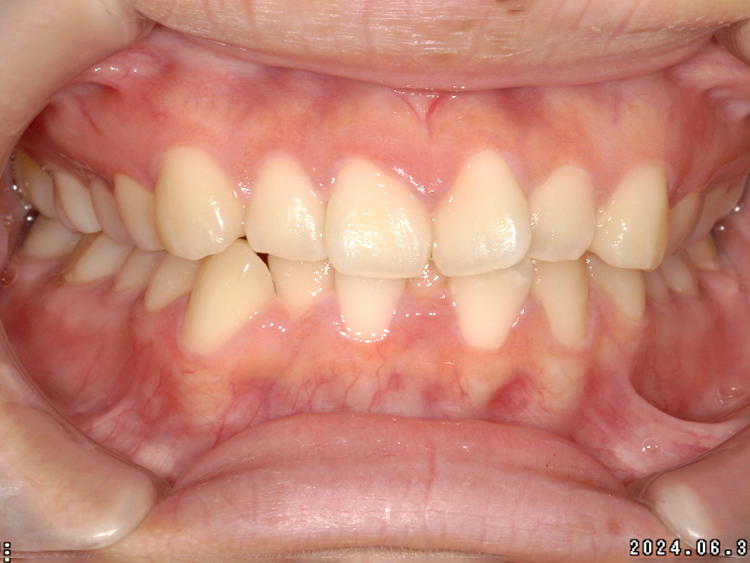

症例4

Before

After

| 主訴 | 上下前歯のがたつき |

|---|---|

| 年齢 | --- |

| 治療 期間 |

約9ヶ月 |

| 治療 内容 |

インビザラインiGoで上下顎の治療。 |

| 治療費 | ¥550,000(税込)/調整料含む |

| 治療のリスク | 矯正終了後は、リテーナーを指示通りに使用し、歯の後戻りを防ぐ必要があります。 |